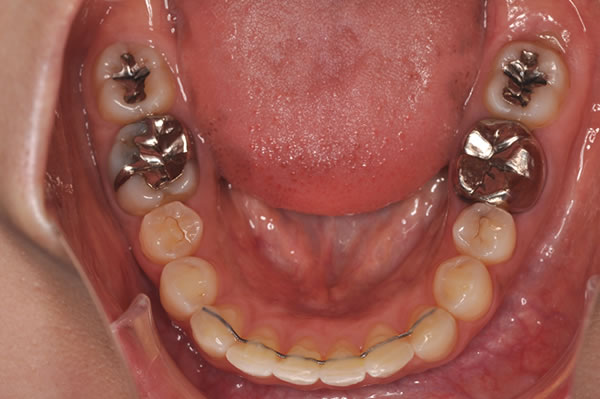

上顎前突症の治療例

上顎前突症(出っ歯)の矯正症例 ケース01

上顎前突症(出っ歯)の矯正症例 ケース02